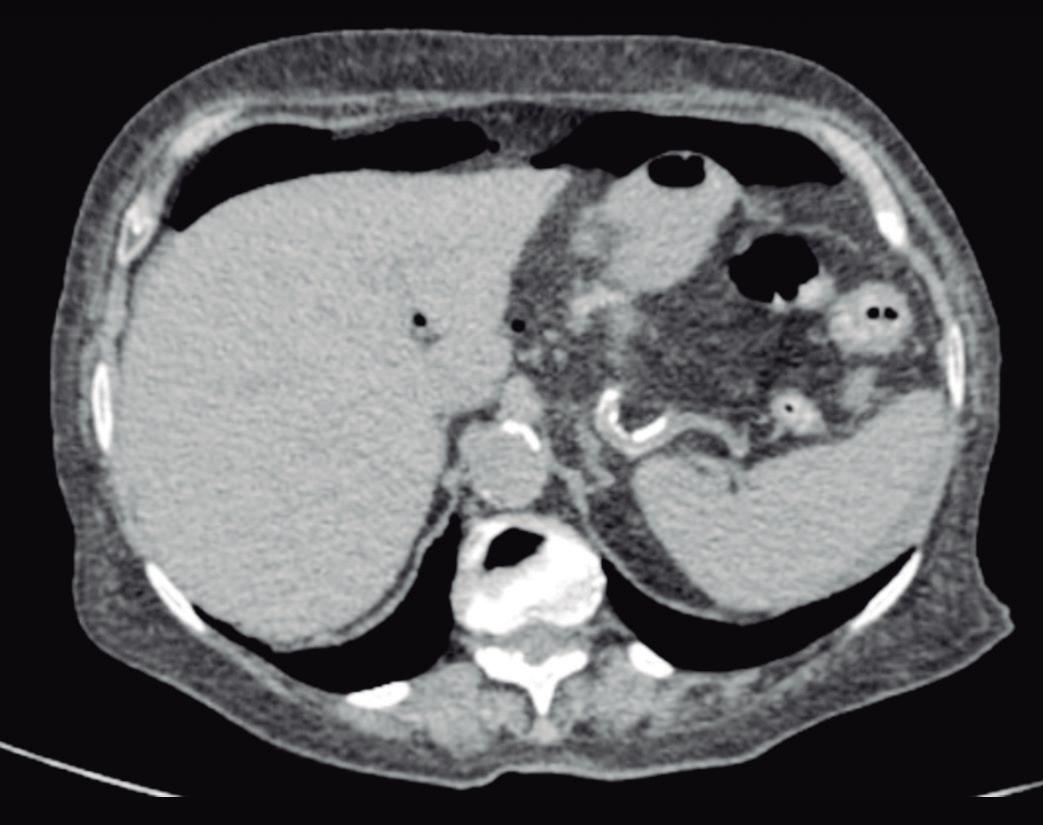

Evaluación endoscópica e histológica

La endoscopía superior es un procedimiento fundamental para el diagnóstico, la evaluación de la respuesta al tratamiento y el monitoreo a largo plazo de la actividad de la EEo. Los hallazgos endoscópicos típicos incluyen edema (reducción de vascularidad), anillos esofágicos fijos, exudados blancos, surcos longitudinales, estenosis, estrechamiento de la luz esofágica, friabilidad de la mucosa (mucosa en papel crepé) y una consistencia firme de la mucosa al realizar biopsias (signo de “tracción" o "resistencia”) en pacientes con fibrosis (Figura 1). Estos hallazgos no son patognomónicos y no constituyen un criterio diagnóstico; sin embargo, cuando se evalúa de forma cuidadosa, en la gran mayoría de los casos se pueden observar.19-21

En el panel A se observa un esófago con edema difuso y pliegues longitudinales; en el panel B se aprecia edema con pliegues y exudados blanquecinos; en el panel C se evidencia un estrechamiento luminal acompañado de anillos esofágicos y exudados; y en el panel D se muestra un desgarro mucoso posterior a la dilatación con bujía de Savary, hallazgo esperado tras este procedimiento terapéutico.

Figura 1. Características endoscópicas de la esofagitis eosinofílica